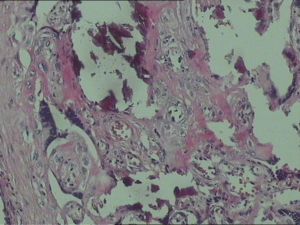

病理

據研究報告顯示,妊娠33周后,一半以上都開始有不同程度的胎盤鈣化現象,此鈣化可從超音波顯示出來,胎盤鈣化與胎兒肺部成熟有關。危害

胎盤鈣化鈣化程度1~3度

依據胎盤鈣化斑點分布的大小與狀況,我們可將鈣化區分為3度。第1度指輕微,而第3度指嚴重。

超音波可約略看出,一般以超音波檢查鈣化的情況不見得準確,若要確認,須根據胎盤娩出後實際檢視胎盤鈣化狀況面積來決定。影響